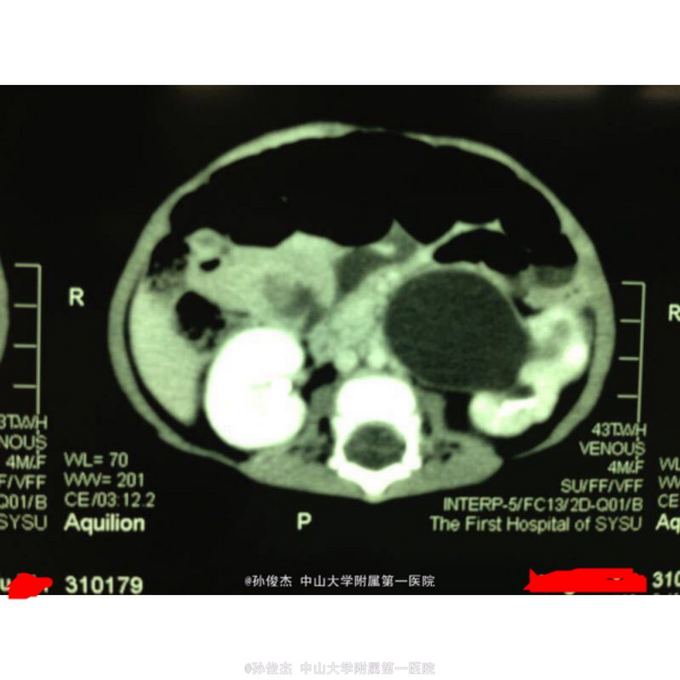

女孩,四个月。产前检查发现左肾积水,出生后超声随访逐渐加重,四月龄时至我院。

超声检查左肾积水5.9*4.3cm,ECT:左肾GFR26.8ml/min明显降低,右肾GFR59.8ml/min正常范围。CT示左肾积水,左肾盂输尿管连接处梗阻。